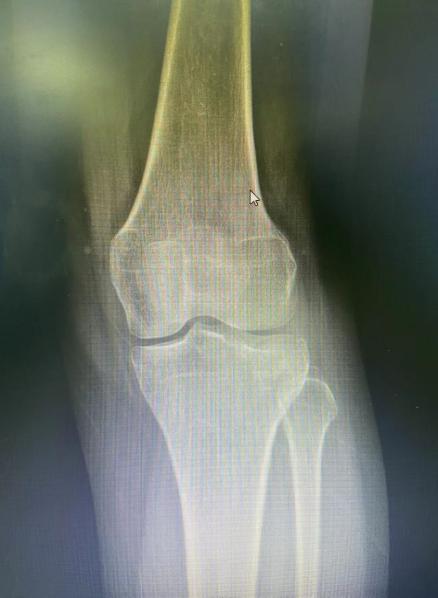

今年26岁的王女士,左膝关节胫骨平台骨折入住我院骨科二病区。

术前X片